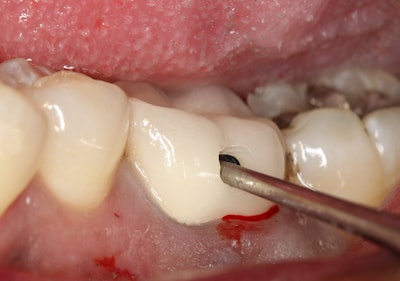

A product I recently evaluated, the WAMkey (Golden Dental Solutions), has changed how I approach the removal of crowns and bridges (figure 4). The Wamkey Intro Kit contains three keys in oval-shaped heads: sizes small, medium, and large.

- Create a small window in the crown that is approximately 1 mm to 2 mm in diameter where the preparation/crown occlusal interface is assumed to be located (figure 5). The opening should be made closer to the occlusal surface for metal crowns and generally about halfway between the occlusal surface and the margin for porcelain or PFM crowns.

- Locate the crown occlusal interface. In most cases, the interface is located in the previous step, but, if not, the opening made in step 1 would have to be progressively enlarged until the cement seal becomes visible. Visual assistance devices such as surgical loupes or a microscope can be extremely helpful in this process. It is critical that you are working in the cement layer.

- Create a tunnel between the preparation's occlusal surface and the inner side of the crown (figure 6). Using a cylindrical bur (approximately 1.2 mm in diameter is recommended), an oval-shaped tunnel between the preparation's occlusal surface and the inner side of the crown is made. The difference in hardness between the dentin and the crown's structure will help the dentist ascertain the bur's position with regard to the dentine.

- Insert WAMkey into the tunnel and rotate with fingers to loosen the crown (figures 7 and 8). Simply insert the key all the way to the end of the tunnel drilled in step 3 and rotate it with a quarter turn with your fingers. If the tunnel was properly drilled, this movement should occur in the long axis of the preparation. Once the crown or bridge is removed (figure 9), it can be used as a temporary or placed permanently if so desired.